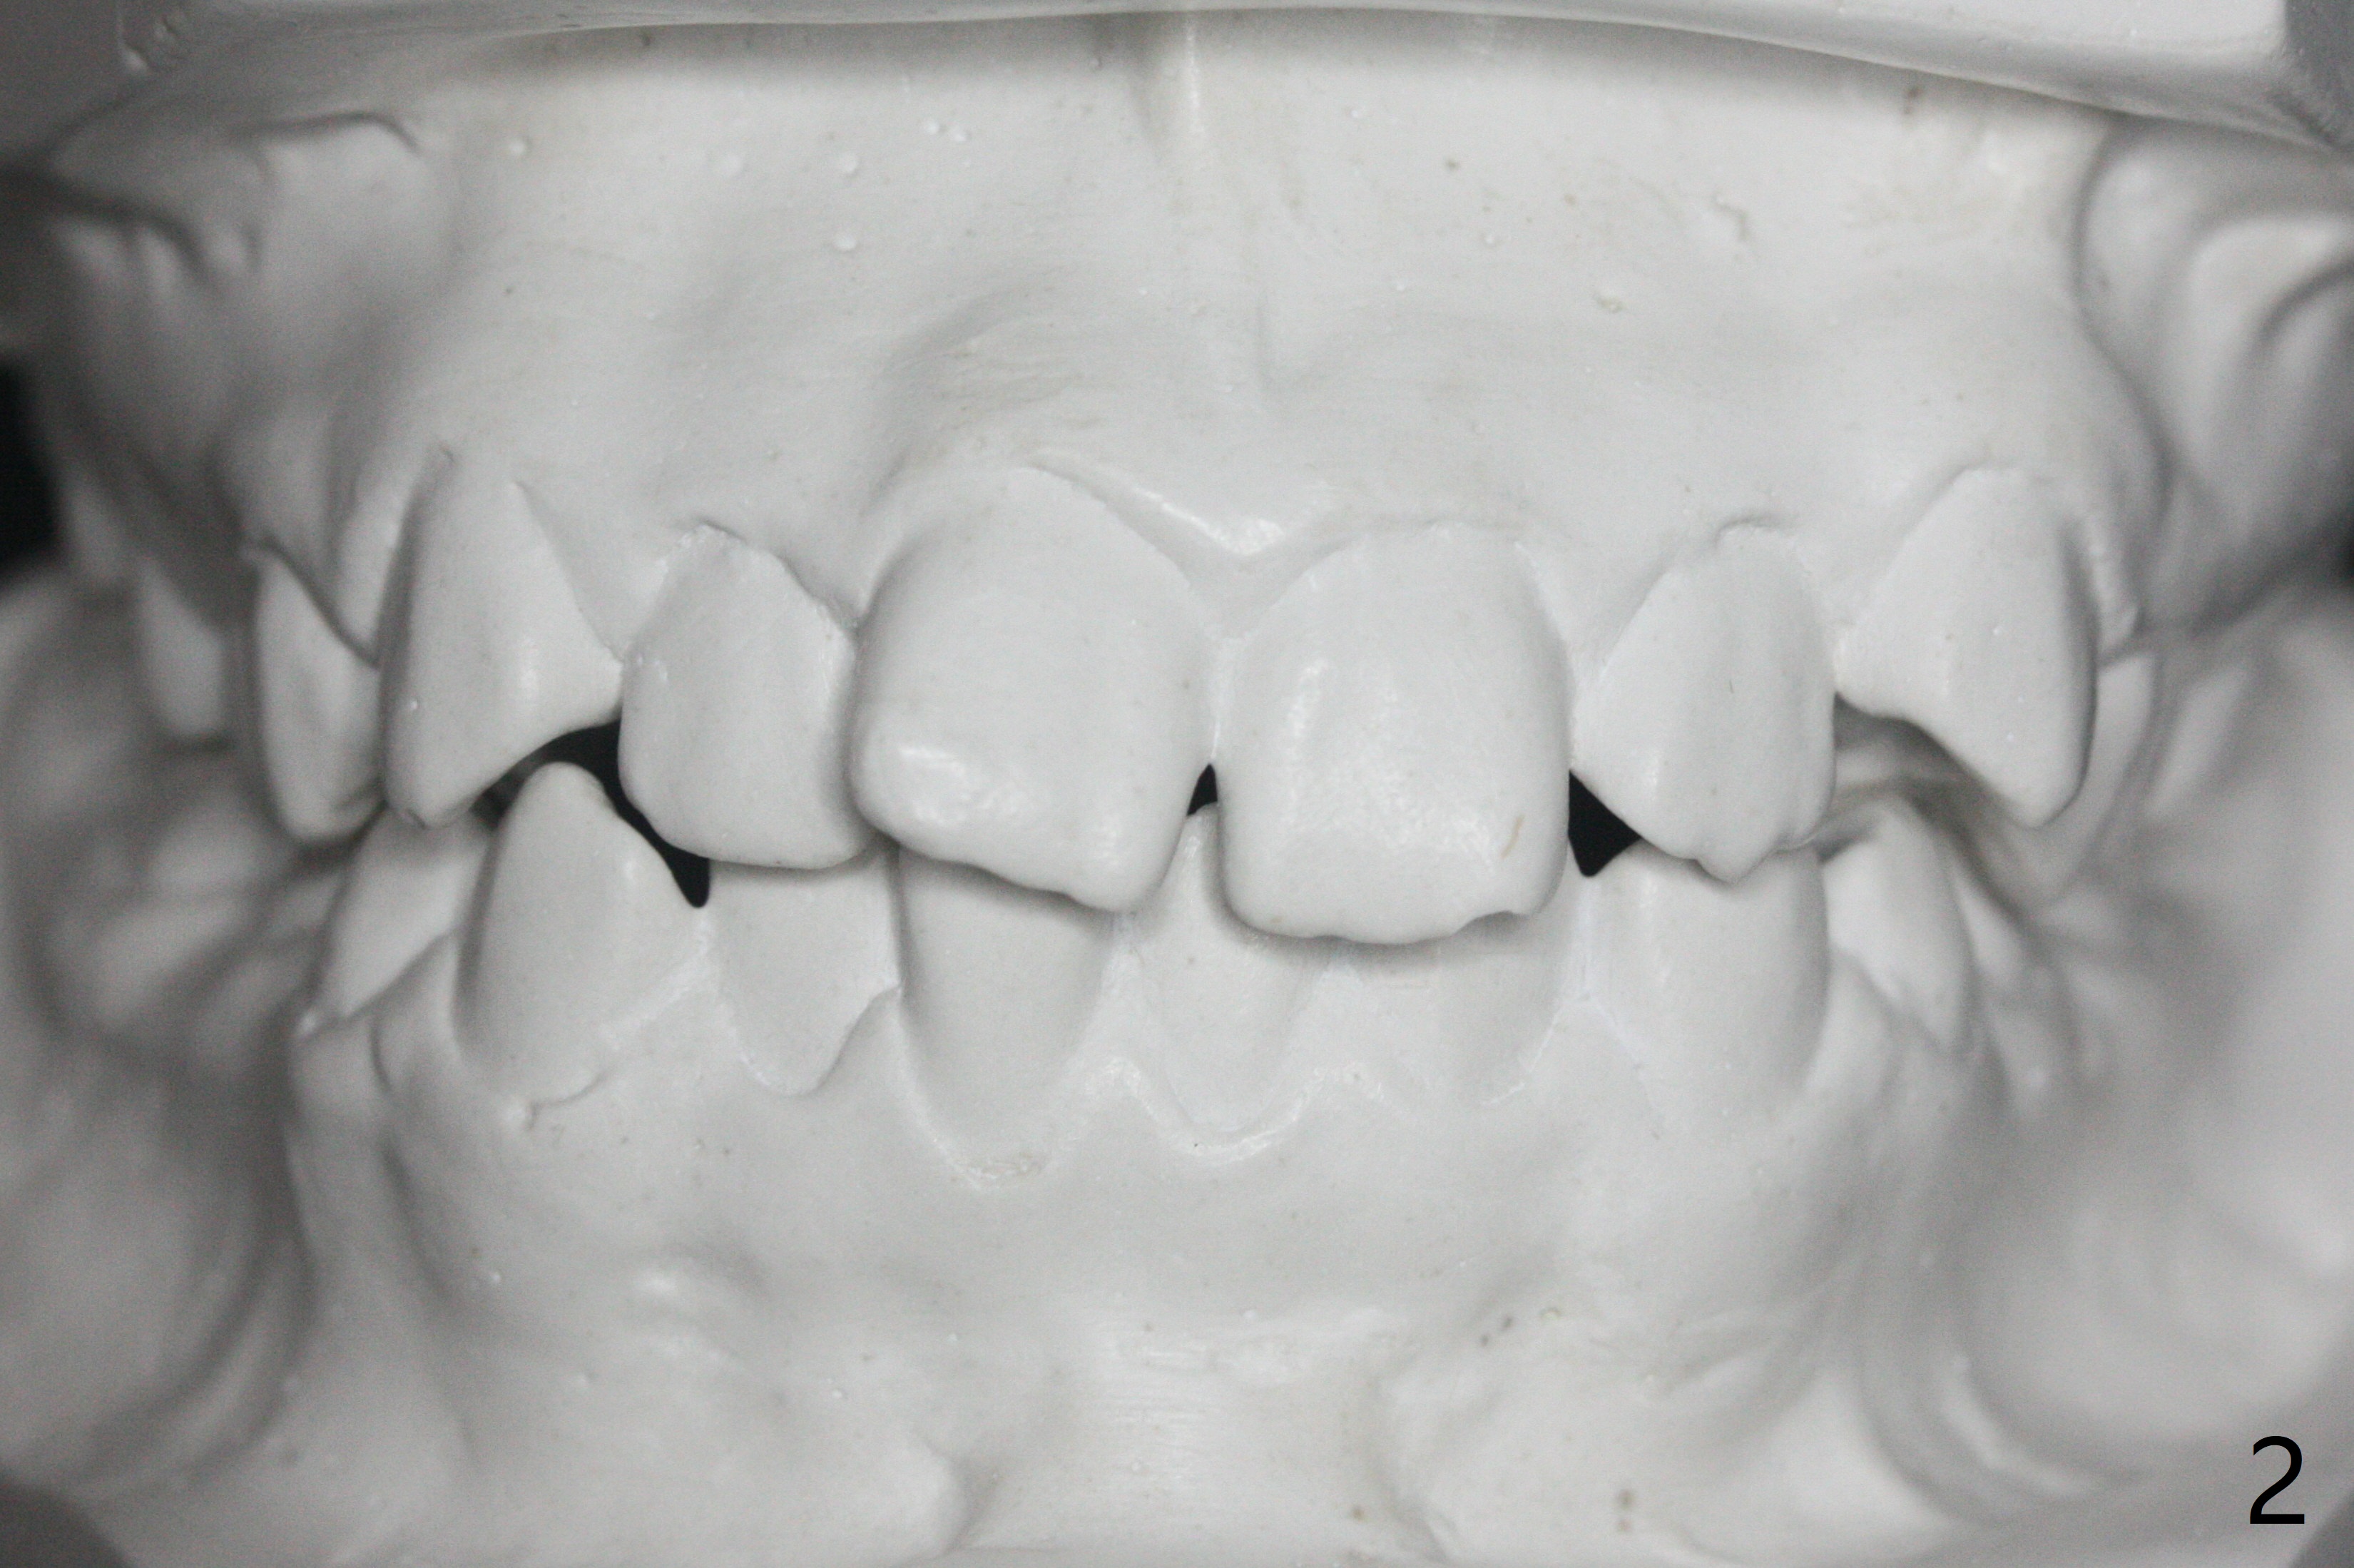

A 12-year-old woman has severe crowding including UL7 impaction (Fig.1-5), finishes non-extraction orthodontics at the age of 15 (Fig.1'-5') and returns for retainer remake at 19 (Fig.1''-5''). Four years post debanding, UL7 (Fig.4') seems to improve its position (Fig.4'').